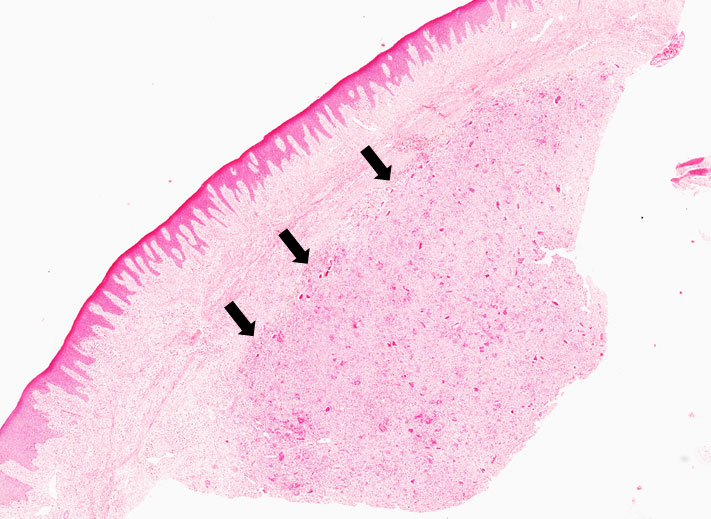

9.1 Hiperplasia inflamatória

Descrição

Fragmento de mucosa bucal revestida por tecido epitelial estratificado pavimentoso hiperceratinizado e hiperplasiado. Na lâmina própria, constituída por tecido conjuntivo denso observa-se exuberante deposição de fibras colágenas dispostas aleatoriamente. Focos de infiltrado inflamatório linfoplasmocitário completam o quadro.

Dados importantes para o diagnóstico

Observar o tecido epitelial hiperplasiado com cristas epiteliais alongadas (Figura 1). Infiltrado inflamatório e as áreas de fibroplasia (fibras colágenas espessas e dispersas no tecido conjuntivo — Figura 2).

Figura 1

Figura 2